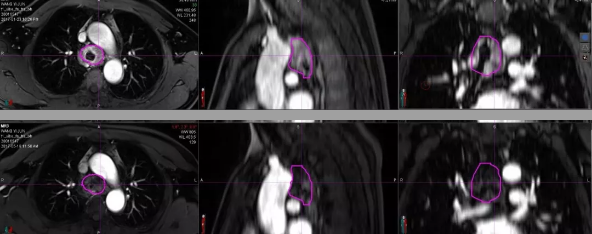

【上图】重离子放疗前

【下图】重离子放疗后3个月

病例B:近隆突处TACC,放疗后3个月肿块大小与放疗前相仿,但MRI(磁共振)显示信号增强程度显著降低,疗效评价为疾病稳定。